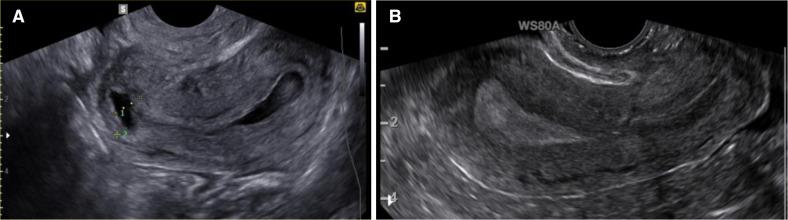

The LAPRES study is a randomised, non-blinded, controlled trial, including 200 infertile women with a total follow-up of 2 years. Women with the presence of a large niche in the uterine caesarean scar and unexplained infertility of at least 1 year or failed IVF will be randomly allocated to a laparoscopic niche resection within 6 weeks or to expectant management for at least 9 months. A large niche is defined as a niche with a depth of >50% of the myometrial thickness and a residual myometrium of ≤3 mm on transvaginal ultrasound. Those receiving expectant management will be allowed to receive fertility therapies, including assisted reproductive techniques, if indicated. The primary outcome is time to ongoing pregnancy, defined as a viable intrauterine pregnancy at 12 weeks' gestation. Secondary outcome measures are time to conception leading to a live birth, other pregnancy outcomes, received fertility therapies after randomisation, menstruation characteristics, patient satisfaction, quality of life, additional interventions, and surgical and ultrasound outcomes (intervention group). Questionnaires will be filled out at baseline, 6, 12 and 24 months after randomisation. Ultrasound evaluation will be performed at baseline and at 3 months after surgery.

LAPRES 研究是一项随机、非盲、对照试验,纳入了 200 名存在大子宫憩室且不明原因不孕至少 1 年或体外受精失败的不孕妇女,总随访时间为 2 年。在 6 周内,将这些妇女随机分配至接受腹腔镜下憩室切除术或接受期待管理至少 9 个月。大憩室定义为经阴道超声检查显示憩室深度>50%的子宫肌层厚度,且残余子宫肌层厚度≤3mm。接受期待管理的妇女,如果需要,可以接受生育治疗,包括辅助生殖技术。主要结局是持续妊娠时间,定义为 12 周妊娠时的活胎宫内妊娠。次要结局指标包括妊娠时间导致活产、其他妊娠结局、随机分组后接受的生育治疗、月经特征、患者满意度、生活质量、额外干预以及手术和超声结果(干预组)。在随机分组后 6、12 和 24 个月时填写问卷。基线和手术 3 个月后进行超声评估。